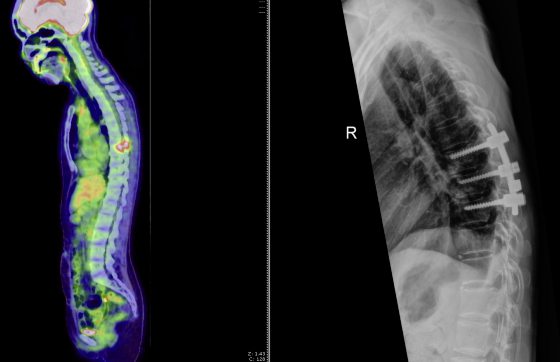

今年5月,我发现自己在深呼吸、打喷嚏或咳嗽时,左胸连带背部会隐隐作痛,于是又做了一次正电子电脑断层扫描,发现第八节胸椎有异状,医生怀疑是癌细胞转移的初步现象。

短短3个月,疼痛加剧了许多,站着痛,坐着也痛,背也有点驼了,磁力共振造影(MRI)显示肿瘤变大了,应该是癌症转移。在这种情况下,我是不是只能开刀治疗呢?

从MRI可以看到第八节胸椎(T8)长了一颗肿瘤,如你所说,肿瘤在短短3个月内变大,侵蚀了1/4的骨骼,椎骨疏松,神经线也被压制,导致疼痛。

这种情况确实需要手术治疗,开刀切除肿瘤,并用螺丝对椎体进行加固。但是,开刀只能切除部分肿瘤,因为有些地方太深入,手术刀难以到达,所以不可能100%切除。